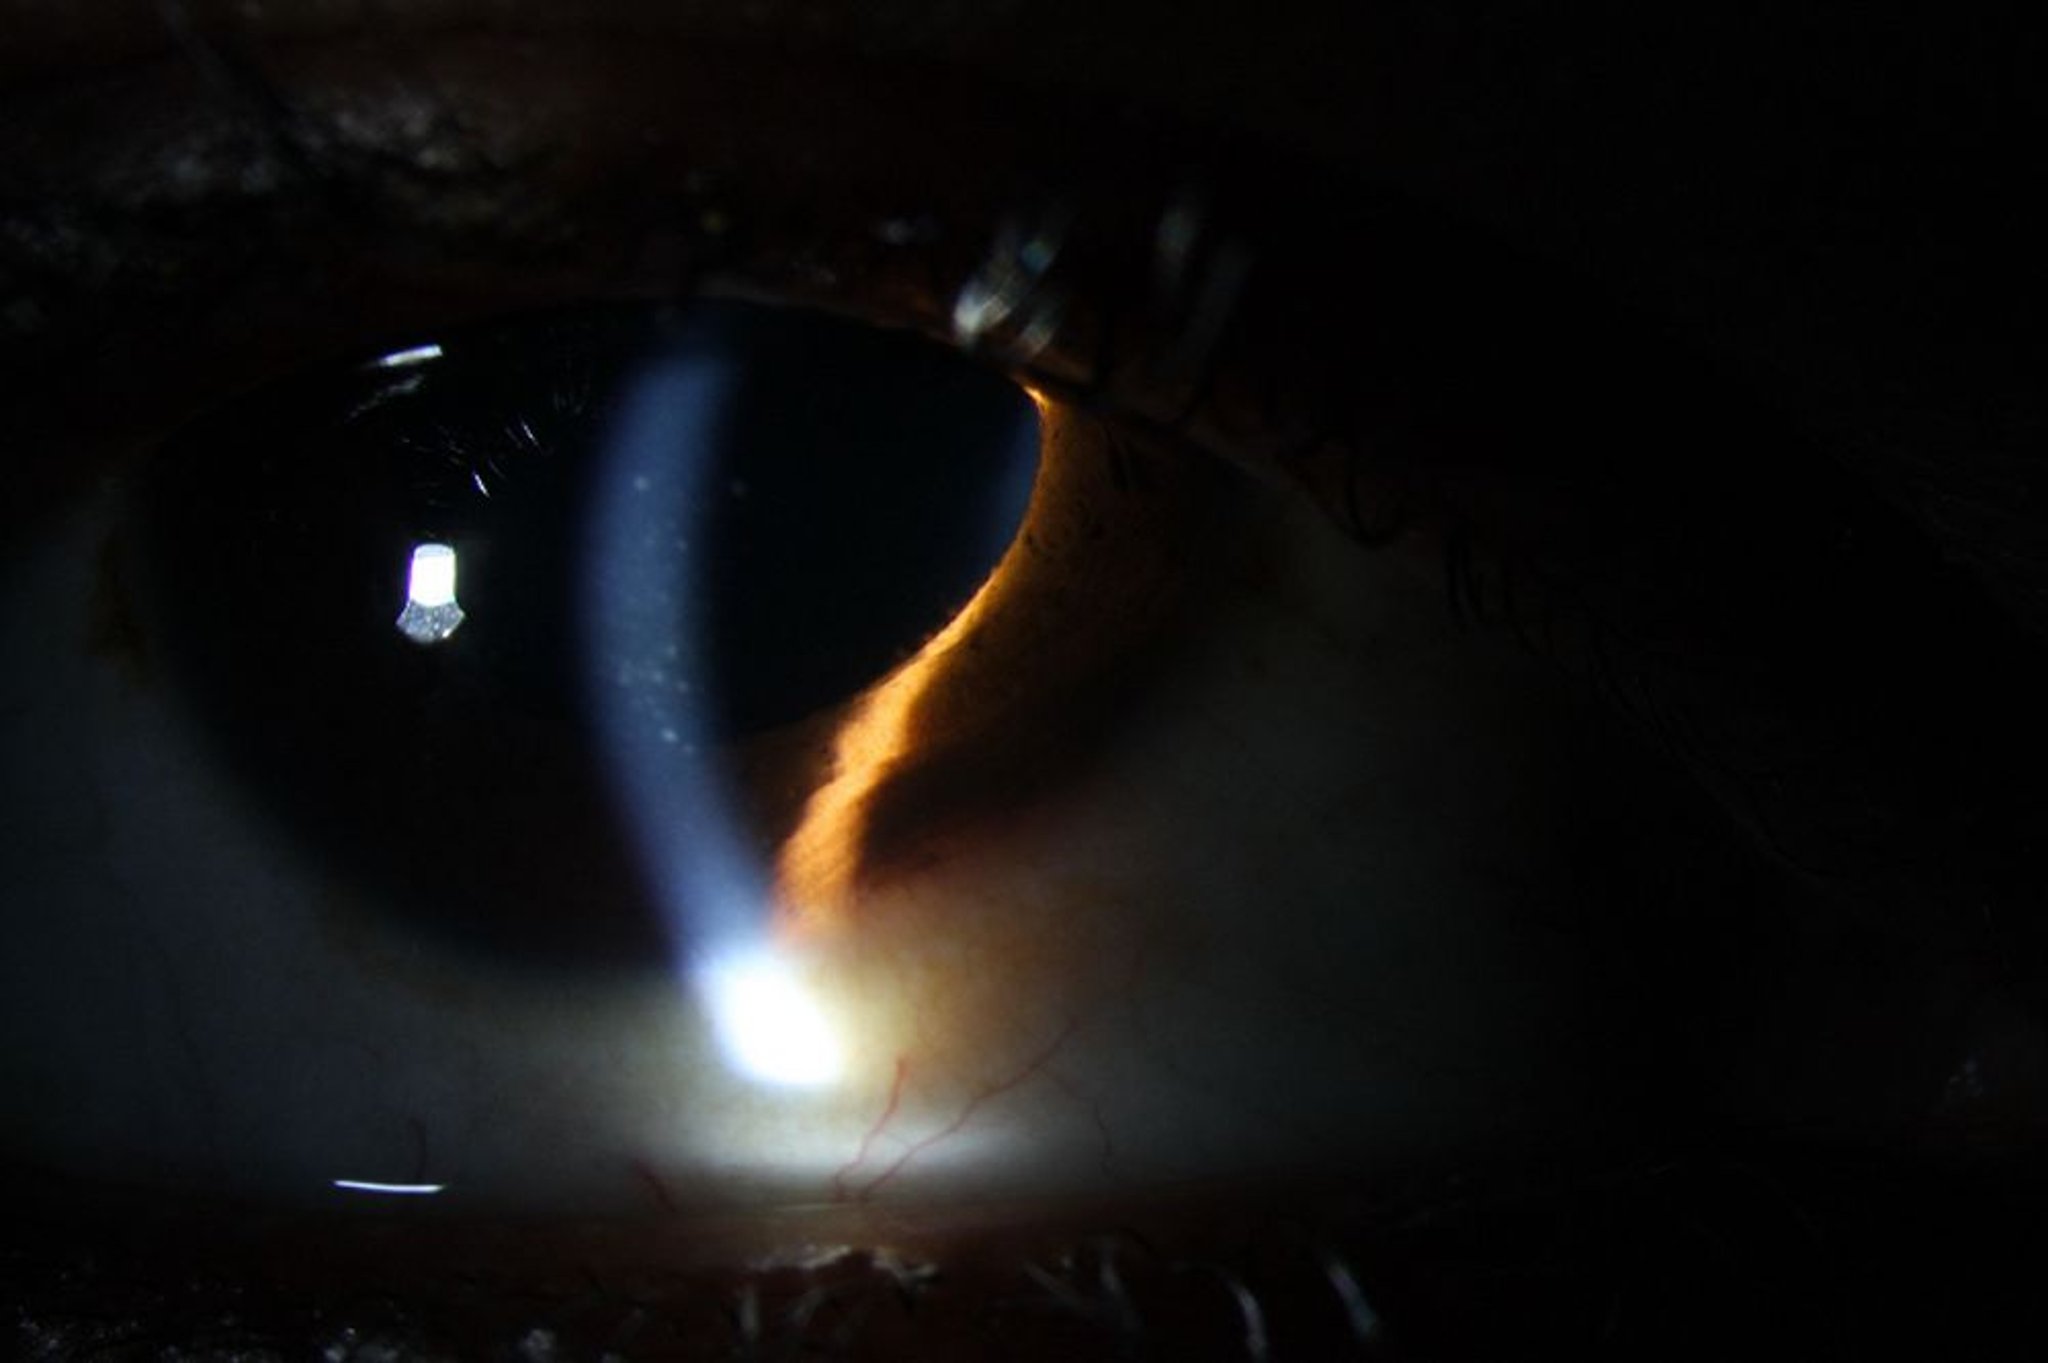

Uveitis (anterior)

Die anteriore Uveitis kann Rötungen, Keratinpräzipitate auf dem Hornhautendothel (im Bild) sowie weiße Blutkörperchen und Flare (Eiweiß) in der Vorderkammer verursachen.

Image courtesy of Sunir Garg, MD.